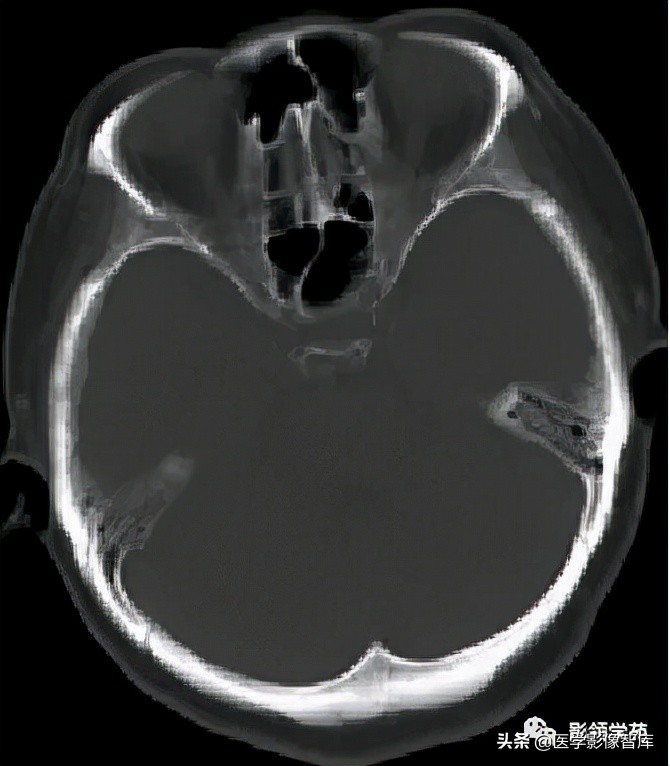

鞍区见一类圆形囊性肿块,囊壁呈蛋壳样钙化。肿块向下压入蝶鞍,向上达到第三脑室水平。

女 58岁,头晕、呕吐,桥脑右前方见一类圆形

高低混合(有血栓)T1及T2信号影,边界清楚、锐利。

明显不均匀强化(瘤内有血栓)。与基底动脉分界不清

头颅CTA:基底动脉起始部血管局部瘤样突起(宽基底),无占位效应。

女 72岁,发现糖尿病3年余

鞍上区见一团块状稍高密度影,边界尚清,密度均匀。

鞍上右上方见一类椭圆形流空影。

病灶明显强化(瘤内血栓未强化),边界清楚,与右侧颈内动脉海绵段分界不清。垂体大小、形态未见异常。